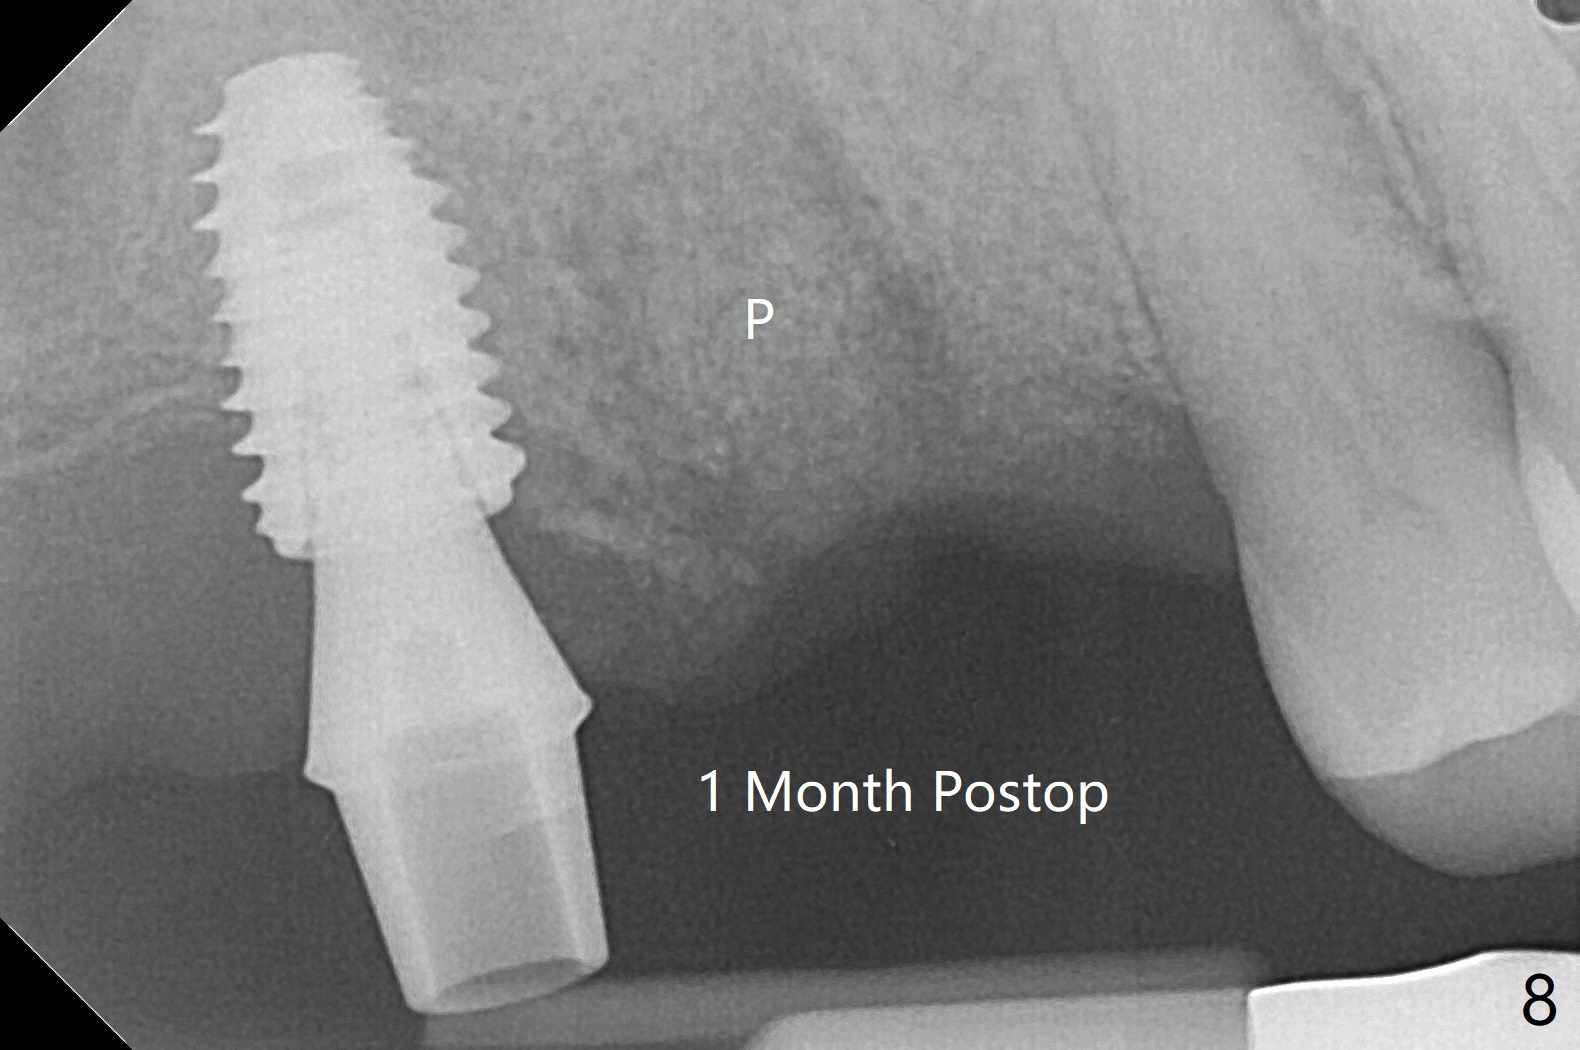

57岁男咬合力大,在右上7植体愈合中,6(3号牙)出现隐裂(图三),根管治疗后完全裂开(图四),需要拔除植骨。由于他特别害怕治疗,包括抽血,开始不想制作粘性骨块,但是考虑到我们最近用的皮质骨粉颗粒细,送到上颌磨牙牙槽窝困难,容易丢失,最后决定抽血提取上清液,制备粘性骨块(图五)。拔牙也有困难,虽然十分松动,但是无法脱位,研究两年前CT,牙根长,弯曲(图一,二),分根后才完成拔除,骨块剪成三块,分别插入三个牙槽窝(图六),覆盖PRF膜和压扁的胶原塞,缝合。术后一个月,角化龈基本保持原位。由于松弛缝合,角化龈有可能增加~6毫米(图七)。而且骨粉好像没有失去(图八,九 (P:腭侧;MB:近中颊侧;DB:远中颊侧))。术后十个月骨质高度降低(图十)。尤其是腭侧,所以植体需要偏向颊侧(图十一:B)。牙冠粘固后8个月,2号牙植体远中骨质吸收(图十二:<)。